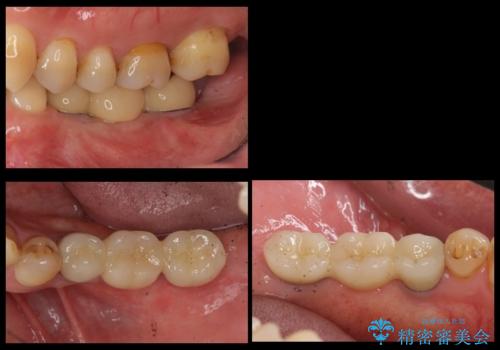

歯並びの改善とインプラントでのかみ合わせの回復 インプラント・セラミック・矯正全顎治療

下顎の部分矯正を行ってから奥歯の補綴治療とインプラント治療